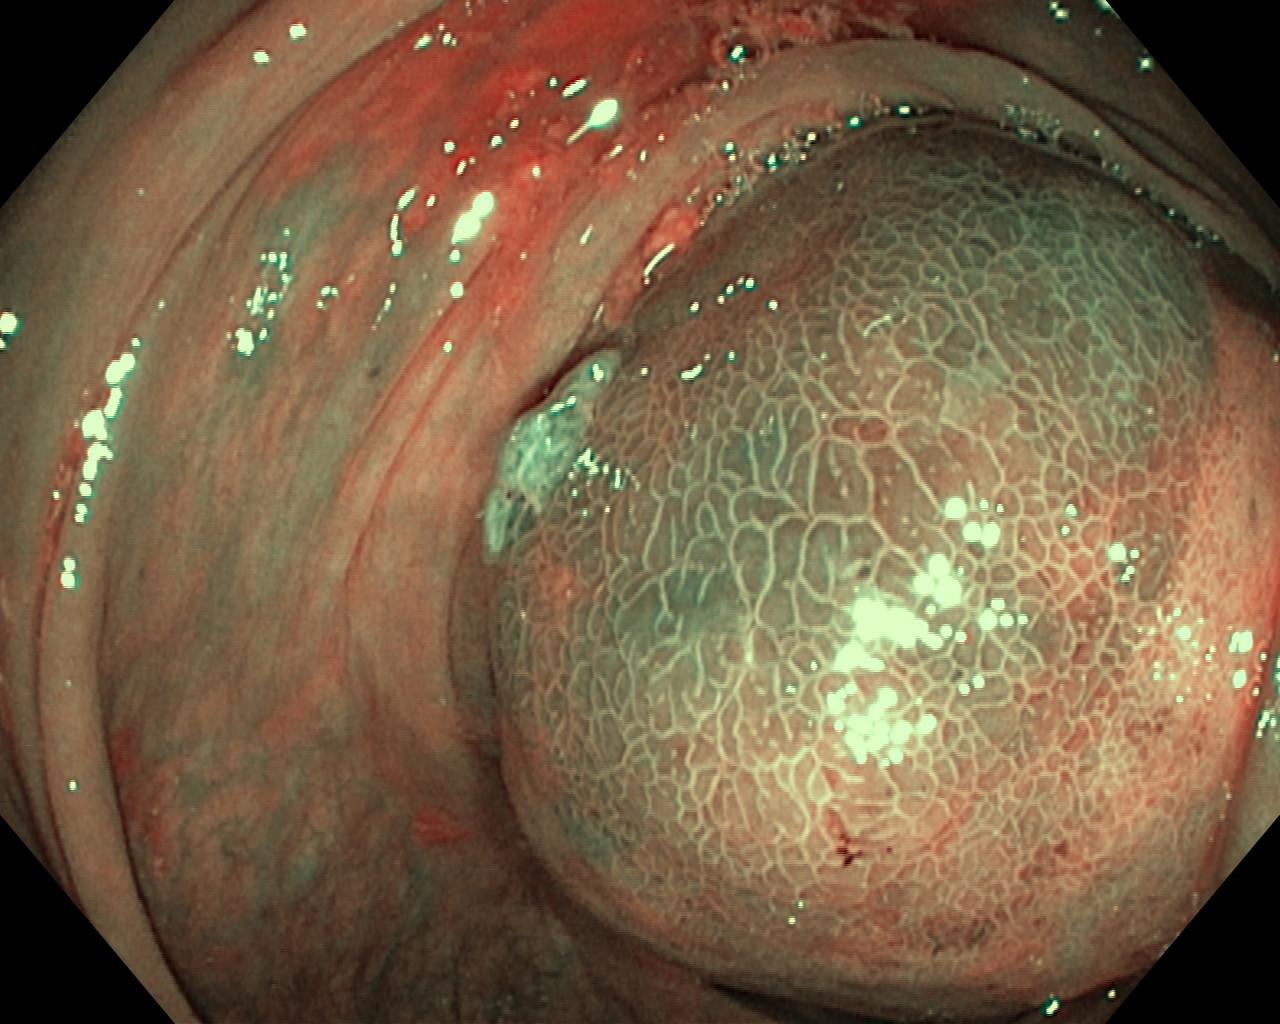

Nowotwory przewodu pokarmowego